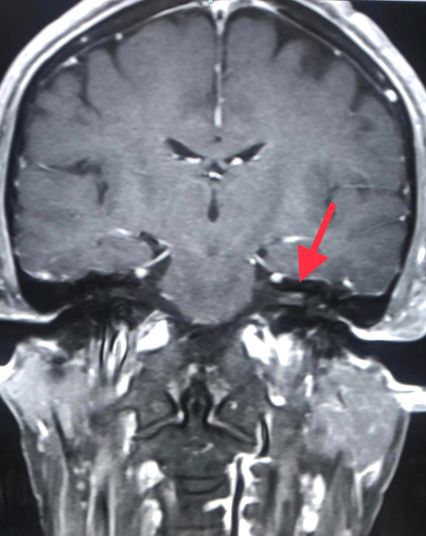

ผลการตรวจคลื่นแม่เหล็กไฟฟ้าสมอง (MRI brain) พบมีการอักเสบของเส้นประสาทในสมองข้างซ้ายเส้นที่ 7 และ 8 เจาะเลือดตรวจแอนติบอดีเฉพาะต่องูสวัด Varicella IgG >5,000 ให้ผลบวก Varicella IgM ให้ผลลบ และเมื่อเจาะหลัง ตรวจน้ำไขสันหลัง พบเม็ดเลือดขาวในน้ำไขสันหลังสูง 188 เชลล์ เป็นชนิดลิมโฟไซต์ (lymphocyte) 100% ค่าโปรตีนสูงเล็กน้อย 58.3 ค่าน้ำตาล ปกติ 76 ส่งตรวจรหัสพันธุกรรม PCR น้ำไขสันหลังพบเชื้อไวรัสงูสวัด (Varicella Zoster Virus )

แพทย์วินิจฉัยว่า ติดเชื้อไวรัสวาริเซลลา (Varicella Zoster Virus: VZV) ไวรัสงูสวัด ซึ่งเป็นไวรัสชนิดเดียวกันกับไวรัสโรคอีสุกอีใส มีอาการแทรกซ้อน เส้นประสาทในสมองข้างซ้ายเส้นที่ 7, 8, 9, 10 อักเสบ และเยื่อหุ้มสมองอักเสบ ให้ยาฆ่าเชื้อไวรัส acyclovir ทางเส้นเลือดนาน 14 วัน และให้ยาเสตียรอยด์ร่วมด้วย